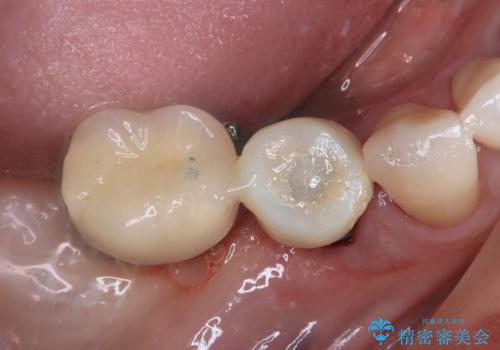

インプラント埋入時に植立具合の安定性を測定したところ、十分な数値が得られたため、速やかに仮歯を装着して咬合回復をさせることができました。

抜歯を含めた外科処置を1回に抑えることができ、あっという間に治療を終えることができました。